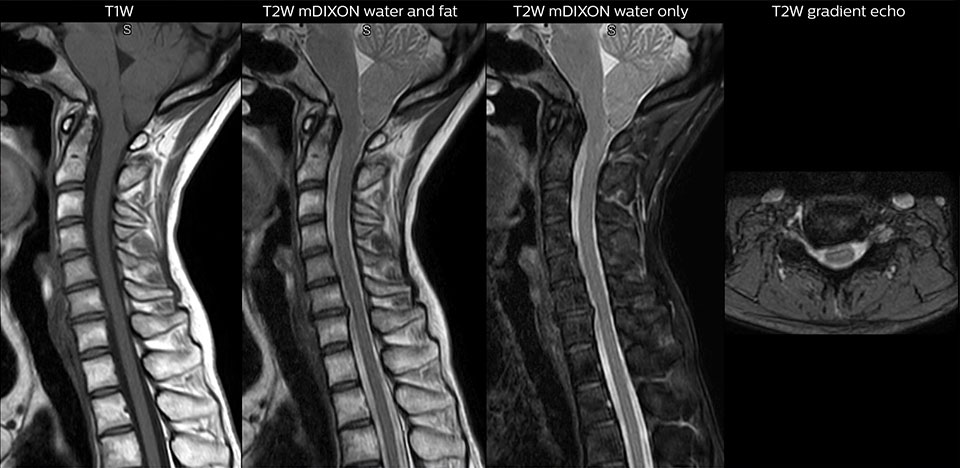

“Pour les examens de routine sans contraste du rachis cervical et thoracique, par exemple, nous réalisons une séquence mDIXON T2 TSE qui produit deux sorties : les images pondérées en T2 avec graisse et eau, et les images sagittales pondérées en T2 avec eau uniquement. Ensuite, nous réalisons également un examen échographique du gradient axial.”

Examen de routine du rachis cervical

Ce patient s’est présenté avec des maux de tête aggravés par la flexion du cou, et on constate une malformation de Chiari de type I avec des amygdales cérébelleuses basses ainsi qu’un changement thrombolytique cervical dégénératif.